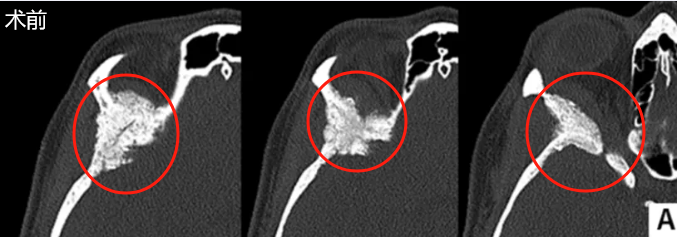

术前MRI和CT显示右侧巨大蝶骨嵴外侧脑膜瘤,伴有慢性钩回疝、脑干受压、中线移位1.4厘米及相关脑积水。术前右眼视力为20/400。患者还存在显著的右侧偏瘫及嗜睡。

患者接受了右额颞开颅术,以进行眶内减压及蝶骨嵠外侧脑膜瘤切除术(视频1)。手术使用切割钻在病变周边异常肿瘤骨与正常额颞骨交界处环行制备多个骨孔。随后使用脚板连接多个骨孔。继而重点处理并磨除异常增厚的肥厚性病变骨质。使用高速切割钻仔细磨除额部、颞部、眶部及蝶骨区受累骨质。

同时通过磨钻去除颞窝内受累的异常肿瘤骨。随后切开硬脑膜,切除硬膜内肿瘤部分及附着硬膜。眶内肿瘤部分通过剥离顺利切除,并切除受累的眶骨膜。最后,采用异体真皮补片覆盖因肿瘤切除造成的硬脑膜大面积缺损区域。